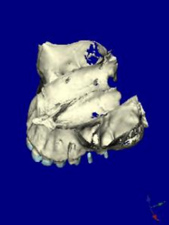

CTデータより3D画像を構築

左上に2本のインプラントを計画

上顎咬合面観